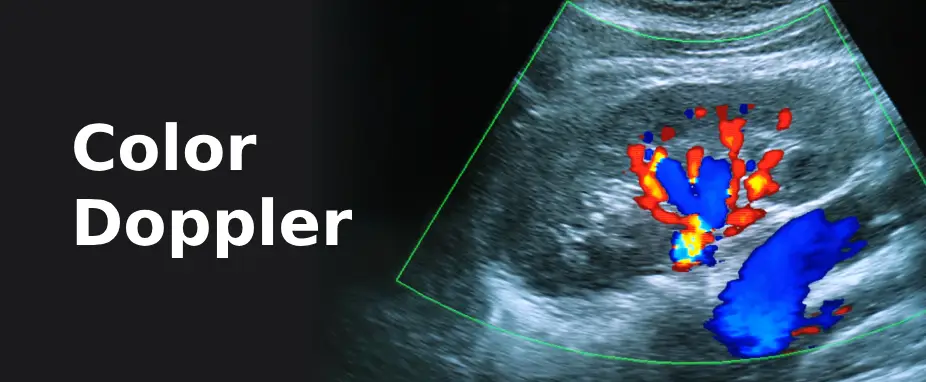

Color Doppler for Advanced Vascular Imaging

Color Doppler is a specialized imaging technique used to visualize blood flow within vessels, helping to detect and diagnose various vascular conditions. At Avantika Hospital, we offer state-of-the-art Color Doppler services to evaluate blood circulation and diagnose issues related to veins, arteries, and organs.

By using high-frequency sound waves, Color Doppler produces real-time, color-enhanced images to assess blood flow dynamics and vascular health. This imaging technique allows for the detailed visualization of blood flow direction, velocity, and any abnormalities, such as blockages, narrowing, or reverse flow, without the need for invasive procedures.

Color Doppler is commonly used for evaluating conditions such as deep vein thrombosis (DVT), peripheral artery disease (PAD), carotid artery disease, and abnormalities in fetal blood circulation during pregnancy. It can also be used to examine blood flow in organs like the liver, kidneys, and heart.